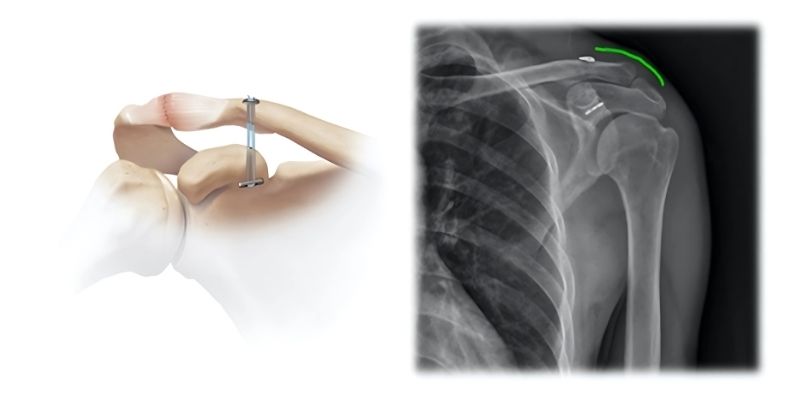

B) Σταθεροποίηση με Ράμματα & Endobutton

- Χρήση ειδικών μη απορροφήσιμων ραμμάτων και μικρής μεταλλικής κατασκευής (Endobutton).

- Δεν απαιτείται αφαίρεση υλικών.

- Πλεονέκτημα: σταθερό αποτέλεσμα χωρίς επιπλέον χειρουργείο.